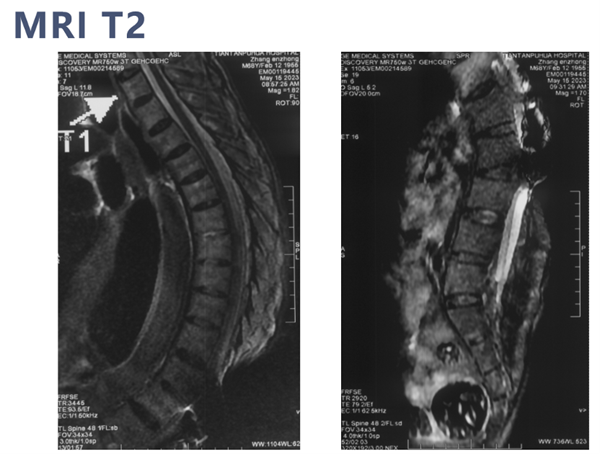

术前影像学检查

MRI